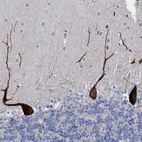

Immunohistochemical staining of human cerebellum shows strong cytoplasmic positivity in Purkinje cells.